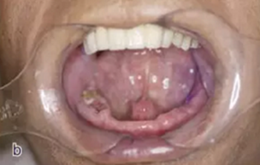

患牙21因根管治療超充,導(dǎo)致根尖周炎,唇側(cè)齲壞并出現(xiàn)瘺管。擬采用即刻種植修復(fù)。術(shù)前拍攝CBCT并做種植方案規(guī)劃,從方案上可知唇側(cè)及遠(yuǎn)中側(cè)骨缺損較為嚴(yán)重,需要同期進(jìn)行引導(dǎo)骨再生術(shù)(GBR)。

圖9 種植方案規(guī)劃:a.近遠(yuǎn)中方向的截面圖,唇側(cè)需要GBR;b.軸向截面圖;c. 模擬植入4.0×13 mm 的種植體